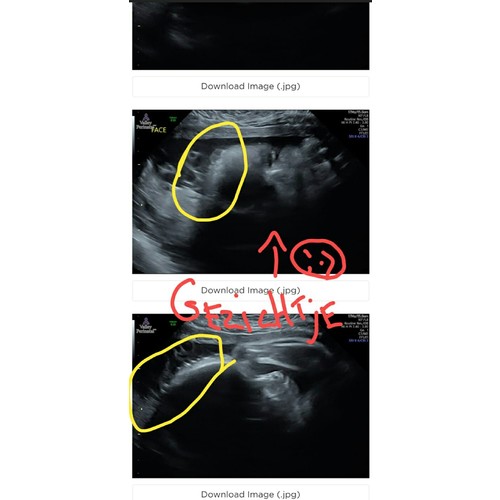

Mijn mamma stuurde mij dit met 1 van de echo s. Het gele omcirkelde zei ze was haar, ik wist niet of dat zo was dus zei we zullen het wel zien. Nou ze had een flinke bos haar toen ze er gisteren uit kwam!